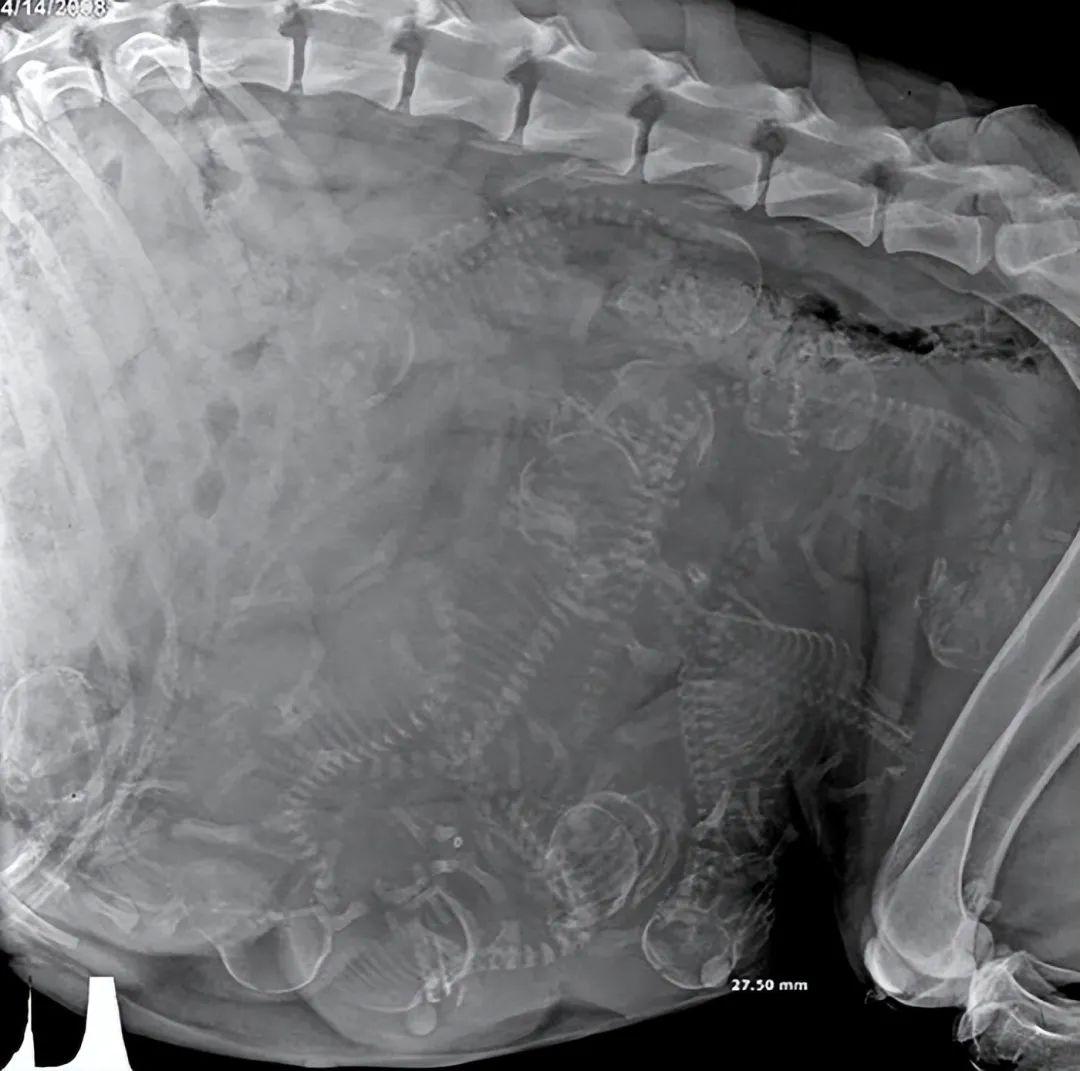

狗狗的X光片里能清楚看到小狗胎兒的輪廓,瞬間讓人心頭一暖。